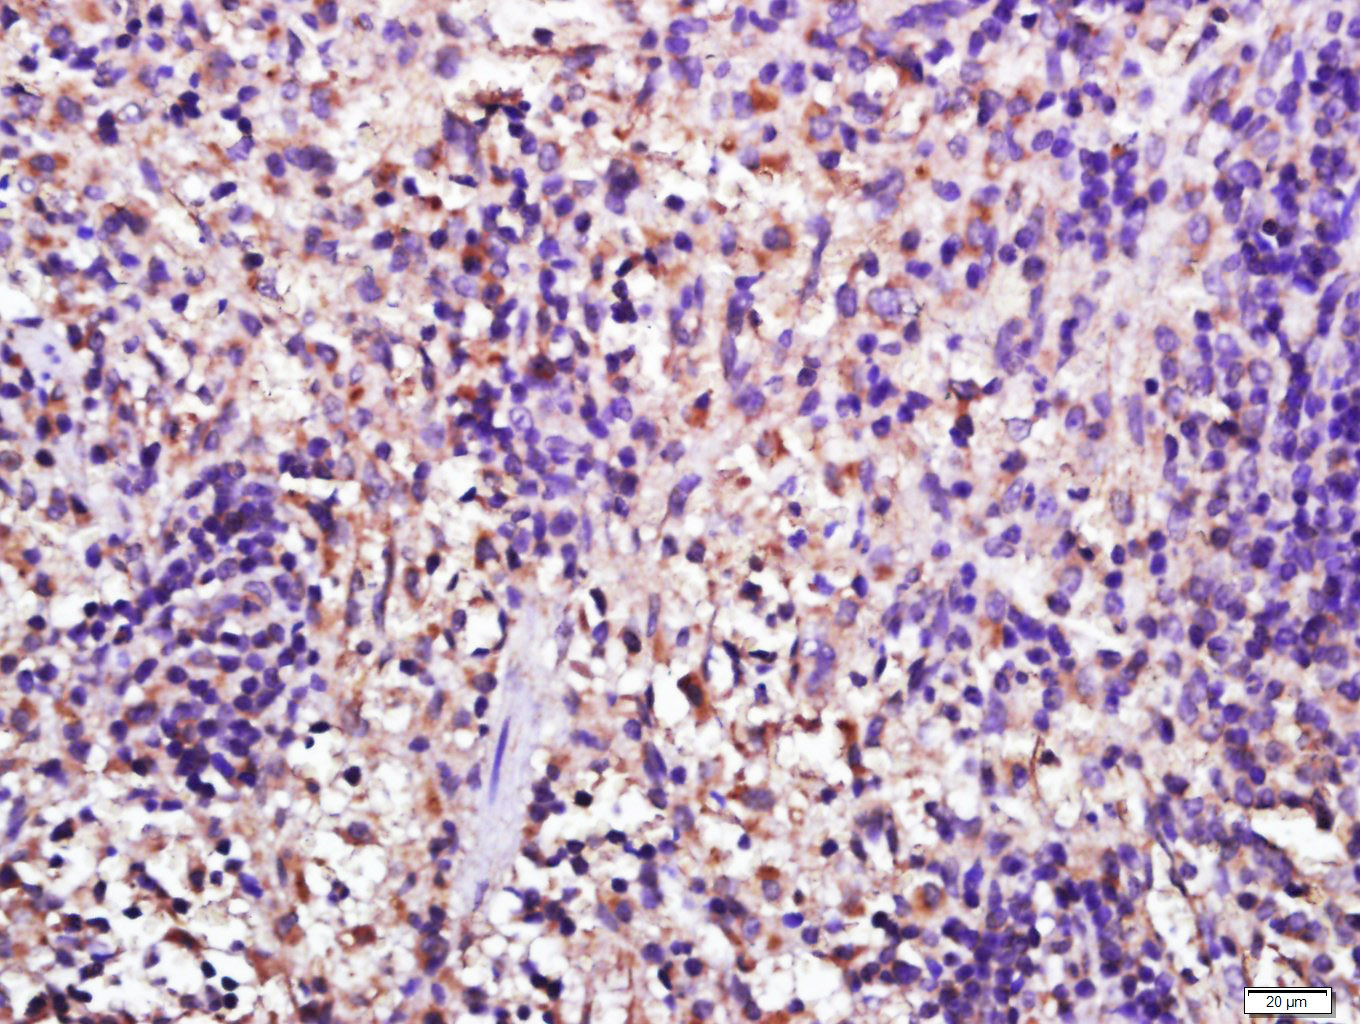

Tissue/cell: Rat lymph node from small intestine; 4% Paraformaldehyde-fixed and paraffin-embedded; Antigen retrieval: citrate buffer ( 0.01M, pH 6.0 ), Boiling bathing for 15min; Block endogenous peroxidase by 3% Hydrogen peroxide for 30min; Blocking buffer (normal goat serum,C-0005) at 37℃ for 20 min; Incubation: Anti-Galectin-3 Polyclonal Antibody, Unconjugated(bs-10377R) 1:500, overnight at 4°C, followed by conjugation to the secondary antibody(SP-0023) and DAB(C-0010) staining

Tissue/cell: Rat spleen tissue; 4% Paraformaldehyde-fixed and paraffin-embedded; Antigen retrieval: citrate buffer ( 0.01M, pH 6.0 ), Boiling bathing for 15min; Block endogenous peroxidase by 3% Hydrogen peroxide for 30min; Blocking buffer (normal goat serum,C-0005) at 37℃ for 20 min; Incubation: Anti-Galectin-3 Polyclonal Antibody, Unconjugated(bs-10377R) 1:500, overnight at 4°C, followed by conjugation to the secondary antibody(SP-0023) and DAB(C-0010) staining

Paraformaldehyde-fixed, paraffin embedded (Mouse colon); Antigen retrieval by boiling in sodium citrate buffer (pH6.0) for 15min; Block endogenous peroxidase by 3% hydrogen peroxide for 20 minutes; Blocking buffer (normal goat serum) at 37°C for 30min; Antibody incubation with (Galectin-3) Polyclonal Antibody, Unconjugated (bs-10377R) at 1:200 overnight at 4°C, followed by operating according to SP Kit(Rabbit) (sp-0023) instructionsand DAB staining.